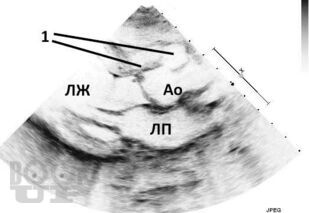

Издание содержит многочисленные рисунки и схемы, иллюстрирующие расстройства гемодинамики, методы исследования и современные оперативные вмешательства при клапанной патологии. Приведены также нормативные данные о размерах сердца и его структур, что необходимо в практической врачебной деятельности.